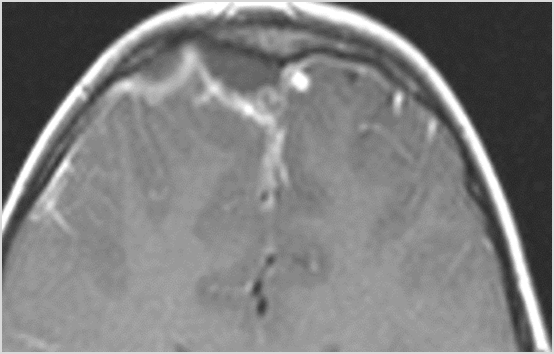

There is evidence of thrombus, thrombophlebitis or other occlusive or inflammatory process of the cortical veins, sphenoparietal sinus or sagittal sinus. [Yes/No]

Findings are consistent with the clinical diagnosis of acute or subacute sinusitis complicated by orbital venous, cavernous sinus or other venous or dural sinus thrombosis.

Findings are consistent with the clinical diagnosis of acute or subacute sinusitis with intracranial complications (specify complications).